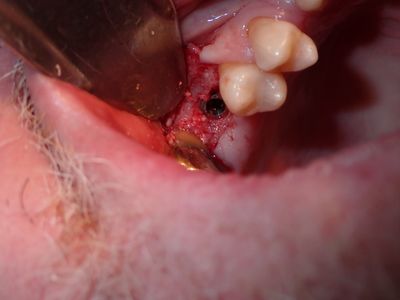

NSankhyan - 16, 26 sinus lift

16 - previous graft and fistula, softer bone, apical bone is into sinus chamber, no perforation of membrane, packed bone, implant placed